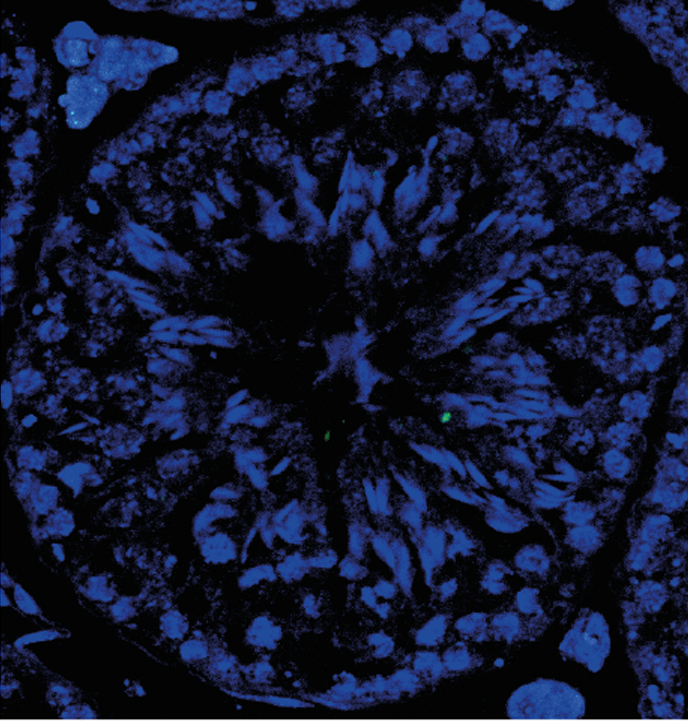

The study demonstrates that RingoA is active at telomeres—structures that protect the ends of chromosomes and where Cdk2 is also found. During meiosis, telomeres allow chromosomes to attach to the nuclear membrane, thus allowing them to exchange DNA fragments. This recombination of chromosomes is an essential feature of meiosis.

Without the RingoA-Cdk2 complex, the telomeres of the chromosomes do not tether to the membrane but rather float in the nucleus, leading to chaotic recombination. The breaks in DNA needed for fragment exchange are not repaired and thus meiosis is not completed. Consequently, sex cells are not formed.